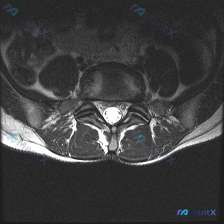

拿到这份资料:临床怀疑椎间盘病变,只提供了一张腰椎MRI T2加权轴位图像,我整理了分析思路跟大家分享。

这是腰椎L3/4或L4/5椎间盘水平的轴位片,影像可见:

- 解剖结构:中央硬膜囊脑脊液信号正常,椎体后缘轮廓清晰,两侧关节突关节间隙对称,黄韧带无明显增厚钙化,椎旁软组织无异常

- 椎间盘情况:髓核T2信号在正常范围,没有明显脱水变性,椎间盘后缘形态规则,没有向后方或侧方的局限性突出/脱出

- 椎管神经情况:中央椎管形态正常,前后左右径无狭窄,硬膜囊形态饱满没有受压;双侧侧隐窝空间清晰,没有狭窄,神经根没有受压迹象

- 其他:没有椎体滑脱,没有椎管内占位,没有明显炎性改变

针对核心问题「椎间盘病变」,从这张片子来看:本层面没有发现支持椎间盘病变导致神经压迫的影像学证据,既没有突出脱出,也没有椎管狭窄,椎间盘也没有明显退变信号。